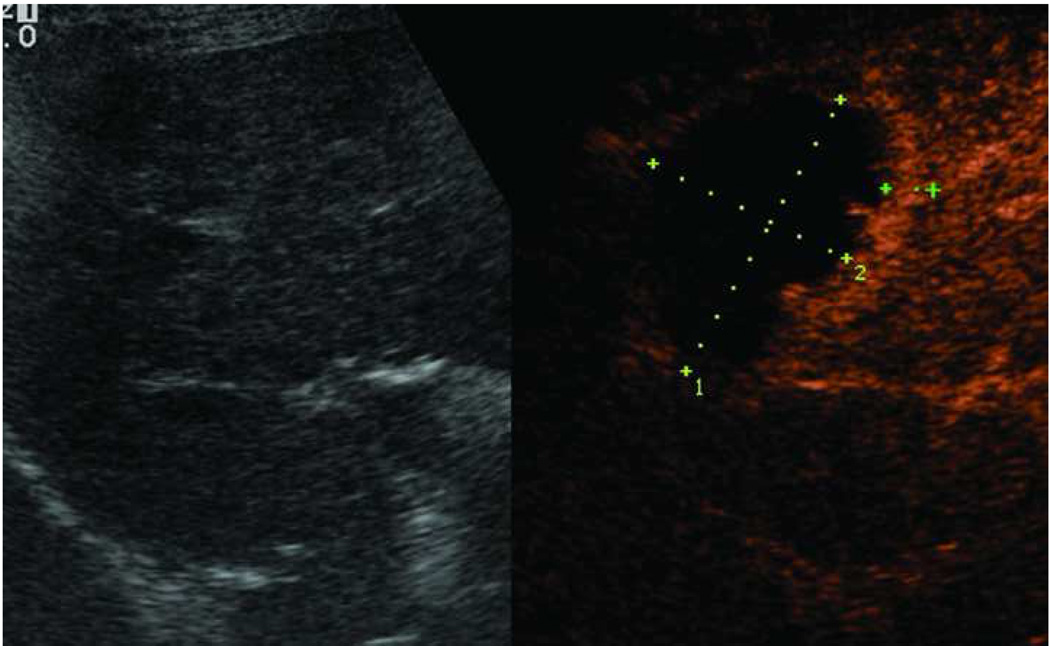

In Europe, the Acculis Microwave Tissue Ablation system consists of a 2.45 GHz generator, with power output settings ranging from 30–100 W, and a percutaneous 15-gauge cooled antenna. The HS Amica microwave system uses a 2.45 GHz generator, with power output to 100 W (60 W recommended output) through 14-gauge and 17-gauge water cooled applicators (Figure 10).

Figure 10.

Microwave ablation performed with HS Amica System. Pre-procedure CT demonstrates nodular arterially enhancing lesion in the posterior right hepatic lobe (arrow, a), redemonstrated on contrast enhanced pre-procedure ultrasound (b). Three sequential placements were performed with an antenna powered at 60 W for 15 minutes each. This produced an ablation zone nearly 7 cm in maximal diameter, as seen on post procedure US (c) and CT (arrow, d). Case courtesy of Drs M. Franca Meloni and Anita Andreano, University of Milan-Bicocca.